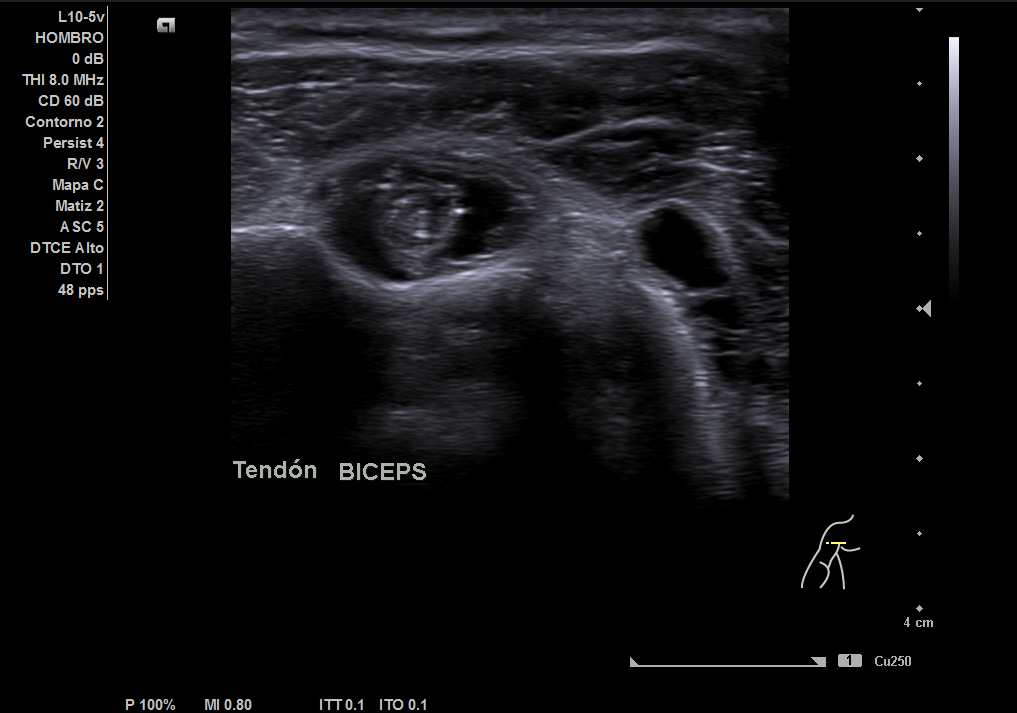

Descripción de los hallazgos ecográficos y las imágenes más relevantes para la resolución del caso

En la ecografía realizada observamos una rotura completa del tendón supraespino, rotura parcial del subescapular y severo derrame peritendón del bíceps junto con derrame articular glenohumeral.